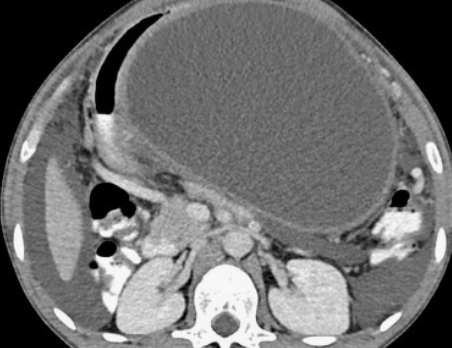

췌장은 다른 장기에 깊숙이 파묻혀 있어 일반적인 복부 초음파검사로 잘 관찰되지 않습니다. 장에 가스가 차 있거나 배가 많이 나온 경우 췌장 자체를 식별하기 어려울 때도 있어, 복부 초음파로 충분하지 않다고 판단되면 CT나 MRI, 내시경초음파 등 다른 검사방법을 고려하게 됩니다.